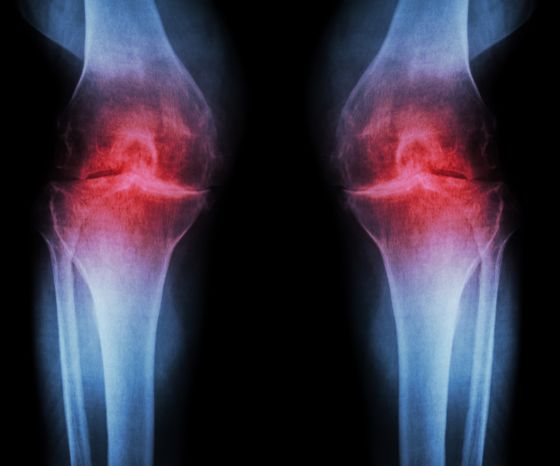

O caracteristică clasică a osteoartritei genunchiului sunt modificările histologice ale calității și grosimii cartilajului articular. O scădere a cartilajului articular duce la hipertrofia osului subcondral și la formarea de osteofite la marginile suprafețelor articulare. O altă consecință este inflamația cronică a țesutului sinovial. Toate aceste modificări duc la suprafețe articulare neregulate, mărire osoasă, posibilă îngroșare a capsulei articulare și în cele din urmă hidrops. Scăderea spațiului articular rezultată este vizibilă pe imaginile radiografice, motiv pentru care vorbim și de "osteoartrită radiologică".

Cel mai frecvent utilizat sistem de clasificare pentru osteoartrita radiologică este scara Kellgren & Lawrence (Kohn et al. 2016):

- Gradul 0: nu sunt prezente caracteristici radiografice ale OA

- Gradul 1: îngustare îndoielnică a spațiului articular și posibilă buză osteofitice

- Gradul 2: osteofite definite și posibilă îngustare a spațiului articular pe o radiografie anteroposterioară cu suport de greutate

- Gradul 3: osteofite multiple, îngustarea clară a spațiului articular, scleroză, posibilă deformare osoasă

- Gradul 4: osteofite mari, îngustarea marcată a spațiului articular, scleroză severă și deformare osoasă clară